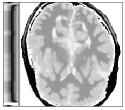

Figure 6 shows examples of the quantitative (magnitude) images of three of the 112 simulated inversion recovery measurements in the test dataset. We also show the regularization parameter-maps for regularization along the spatial directions and along the inversion-time direction generated by the network. The mean PSNR and SSIM of our proposed method is consistently higher for all considered acceleration factors, even compared to PDHG with regularization strength along spatial and inversion-time direction chosen by grid-search with access to the ground truth images (shown in Figure 8 and Table 2). The resulting parameter-maps after performing the regression on the reconstructed images are shown in Figure 7. Again, our proposed method results in the lowest RMS deviation from the ground truth images (Table 2).

CG-SENSE PDHG PDHG PDHG Target/ZF /

Example 1

Example 2

Example 3

CG-SENSE PDHG PDHG PDHG Ground Truth